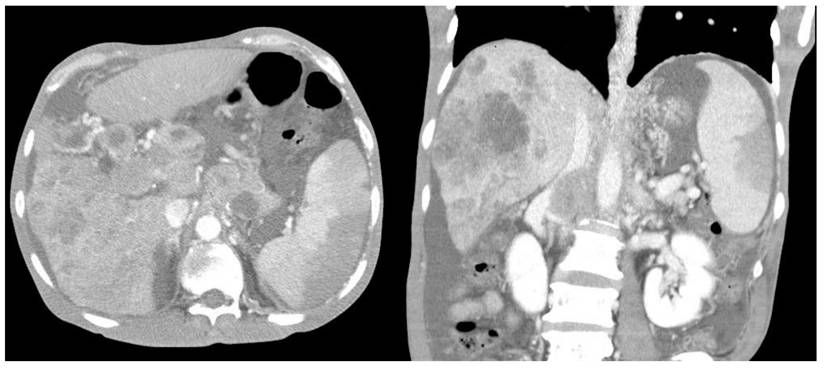

Furthermore, compared with survivors, the non-survivors exhibited significantly higher rates of left-sided pleural effusion, peri-splenic ascites, multiple or total infarction, main portal vein thrombosis, and splenic vein thrombosis on CT imaging. Co-infarctions most commonly involved the kidneys, brain, and intestines. At least one organ co-infarction occurred in 30.6% of cases, while 11.5% experienced two or more, but no significant group differences were observed (Table S4). Figure 2 shows concurrent splenic and left renal infarction, whereas Figure 3 shows splenic infarction with portal vein thrombosis and ascites in a patient with hepatocellular carcinoma.

Figure 3

Splenic infarction in a patient with hepatocellular carcinoma. Contrast-enhanced abdominal CT reveals a wedge-shaped splenic hypodensity consistent with infarction, an ill-defined heterogeneous hypodense mass in the right hepatic lobe, portal vein thrombosis, and ascites.